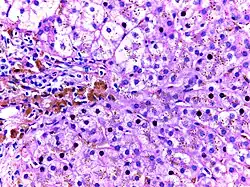

![]() |

Hemochromatosis liver | Micrograph of hemochromatosis liver showing hepatocytes with coarse golden yellow granules of hemosiderin within the cytoplasm. These granules stain with Prussian blue stain. | Category: Histopathology of hemochromatosis | hereditary hemochromatosis |